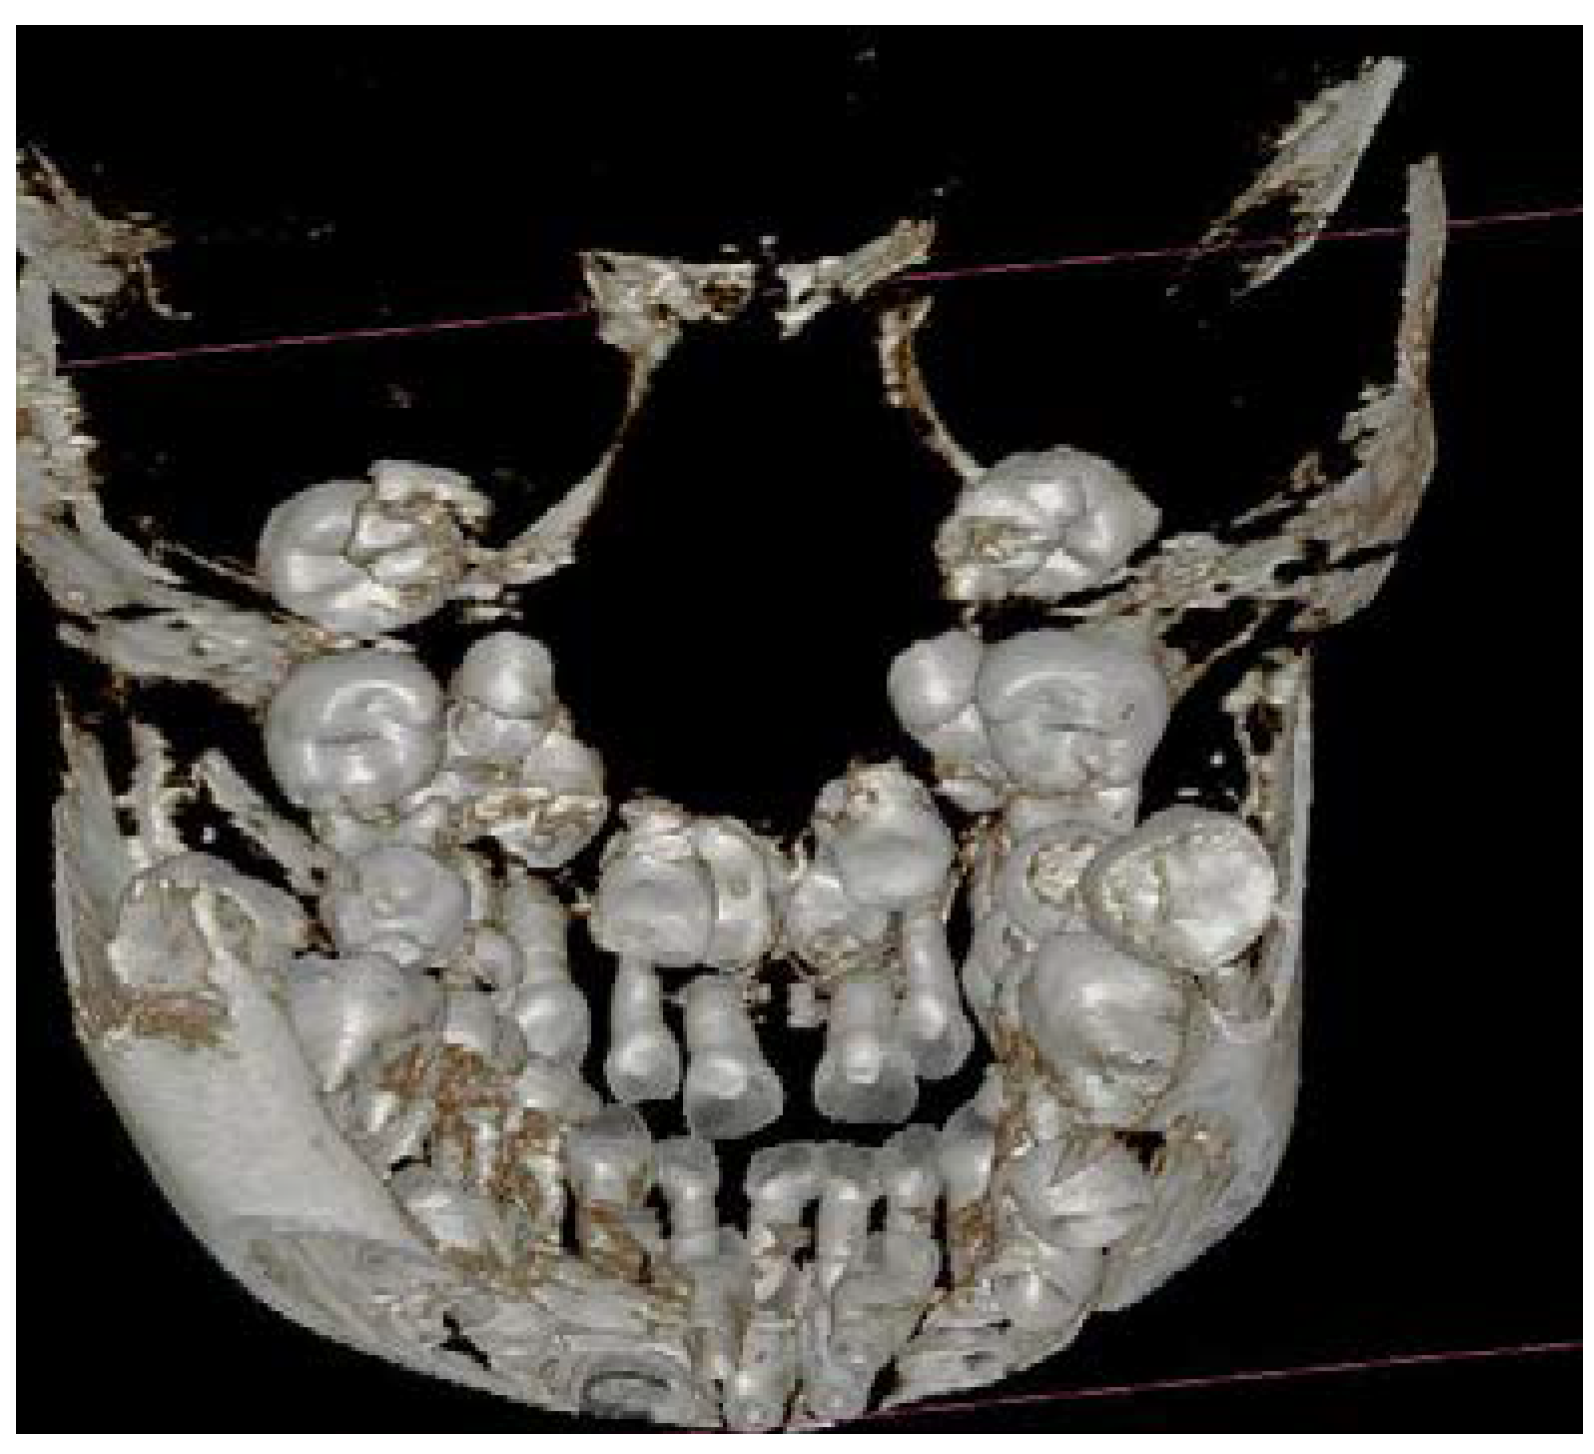

The three-dimensional (3D) reconstruction of the CBCT x-ray, taken in May 2013 revealed three more supernumerary empty tooth crypts in the upper jaw and proved the two supernumerary teeth in the lower. The patient had had 8 supernumerary teeth at that time. (Figure 1.,6.,7.)

Figure 6. Seven supernumerary teeth in the upper arch before the 1st surgical intervention in 2013. 3D reconstruction.